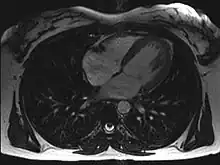

Magnetic resonance imaging (MRI)

Magnetic resonance imaging visualizes the heart by detecting hydrogen atoms using superconducting magnets, particularly those attached to water and fat molecules.[9] These hydrogen atoms possess a property known as nuclear spin. Although the direction of this spin is usually random, the spin can be aligned using a powerful magnetic field.[9] Faint electromagnetic signals are emitted by these hydrogen atoms when their alignment is temporarily disturbed which can be detected and used to create an image of the heart.[10]

Cardiovascular magnetic resonance (MR) technology is able to measure the size, shape, function, and tissue characteristics of the heart in a single session.[11] It is also commonly used to determine ventricular function and for the evaluation of structural heart disease.[12] It is more reproducible than echocardiography with less inter-observer variability, allowing for more precise reference ranges to better distinguish health from disease.[11] Additionally, MR lacks ionizing radiation and does not have any known long-term effects, making it safe for repeated imaging.[13]

Additional benefits from cardiac MRI include the ability to detect scar within the heart using late gadolinium enhancement, and identify other abnormalities of the heart muscle itself such as infiltration with iron or amyloid protein.[11] Disadvantages of MRI include lengthy protocols and the potential for claustrophobia. Furthermore, an MRI scan cannot be performed in some people who have metallic implants such as some types of pacemakers, defibrillators, although many modern pacemakers are safe for use within an MRI scanner.[14] Other metal structures such as artificial valves and coronary stents are generally not problematic. However, MR is less widely available and may be more difficult for patients to tolerate than other noninvasive modalities, requiring physician monitoring for complex cases.[13]